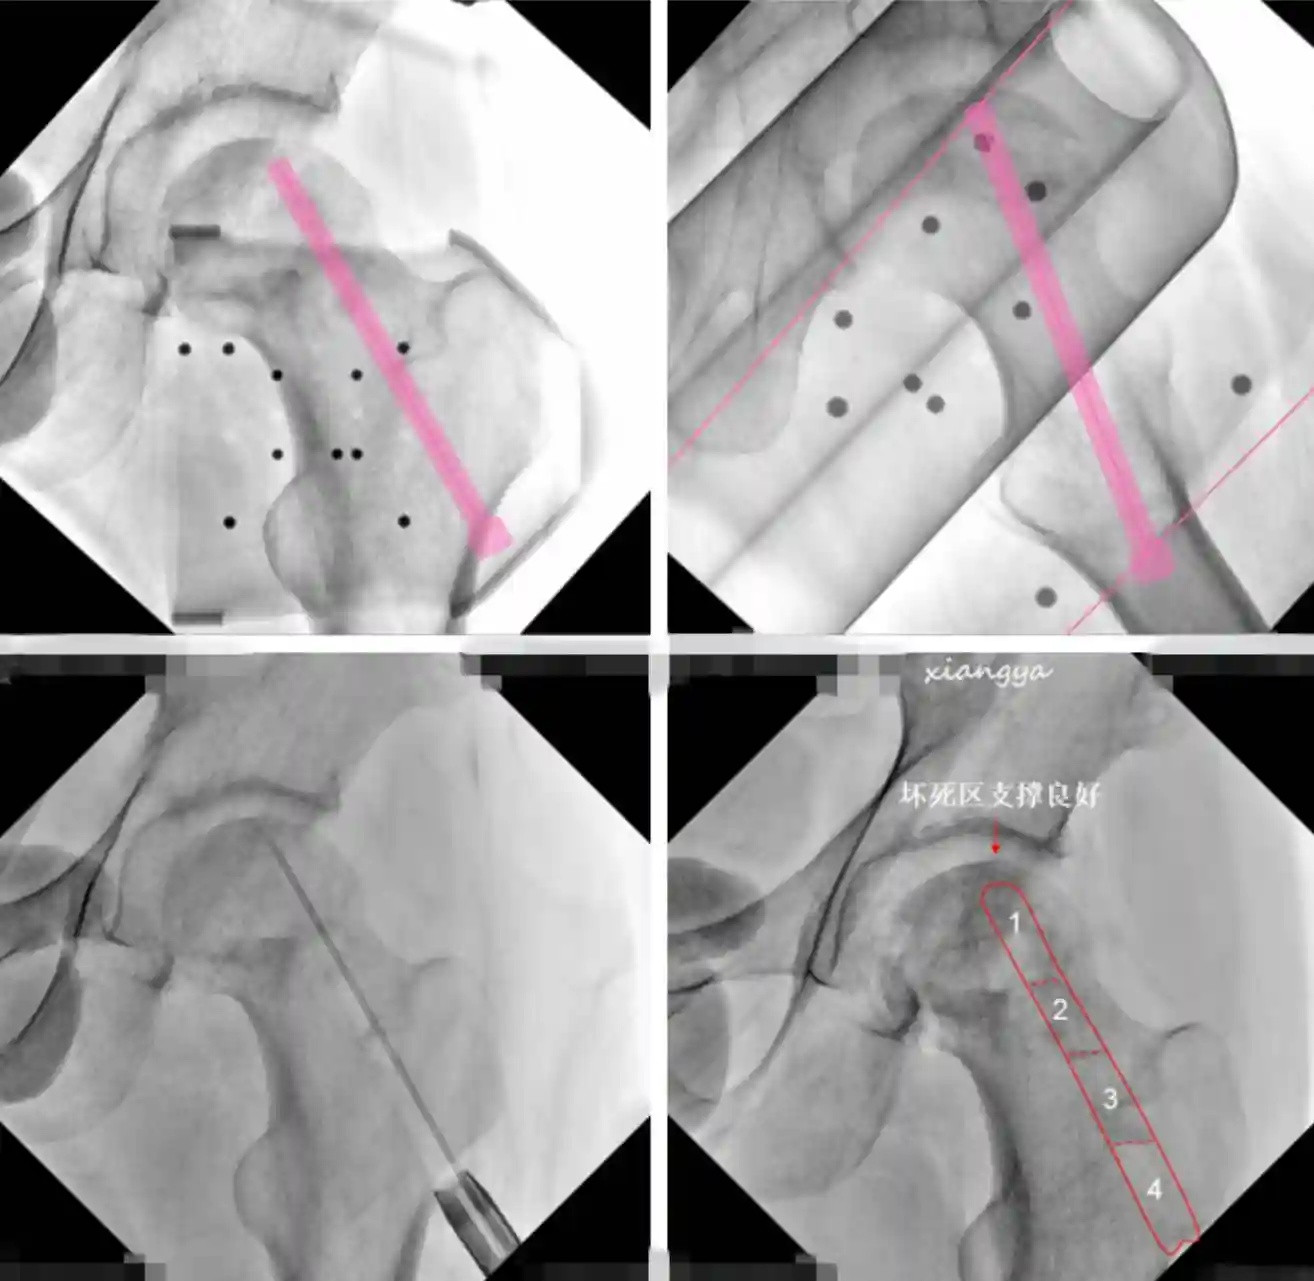

上图:术中机器人定位,导针指向股骨头坏死区;左下:术中按机器人定位隧道,指向股骨头坏死区注入自体PRP;右下:4根髂骨棒植入后,股骨头坏死区支撑良好

经过充分的术前准备,4月12日,高曙光副教授、熊依林主治医师按照预定手术思路,首先根据机器人定位,将导针精准打入股骨头坏死区,用8mm钻制作骨道至坏死区域,再进行髓心减压,将自体PRP(富血小板血浆)注入坏死区域,最后将自体髂骨棒分次植入,为股骨头坏死区提供可靠支撑。随后,髋关节镜探查发现关节内炎性滑膜增生、髋臼盂唇损伤、股骨头颈部Cam畸形,进行炎性滑膜切除、损伤盂唇修整、股骨头颈Cam成型。同时,在髋关节镜可见股骨头坏死塌陷区支撑良好,手术顺利完成。目前患者恢复良好,将于近日出院。

髋关节镜可见股骨头坏死塌陷区支撑良好